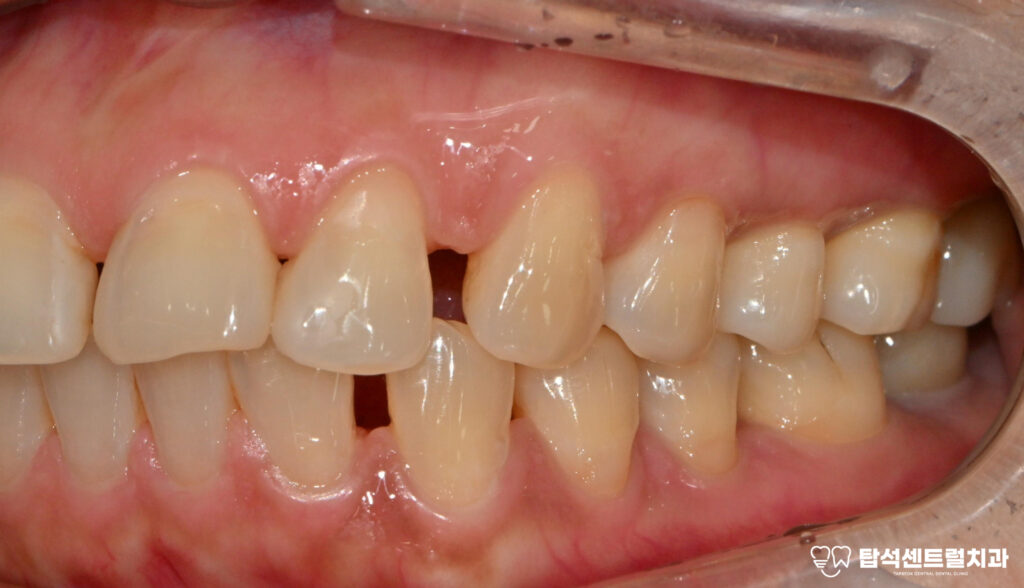

엑스레이 촬영을 통해 구강 상태를

확인하면 치주염으로 인한 전반적인

치조골 소실이 관찰되는 경우가 적지 않습니다.

치조골은 이를 지탱하는 뼈 조직으로

이 부분이 손상되면

치아 동요도가 증가하게 됩니다.

27번과 37번처럼

심한 동요도와 함께

통증을 호소하는 상황에서는

발치를 고려해야 되는 단계에

이르게 됩니다.